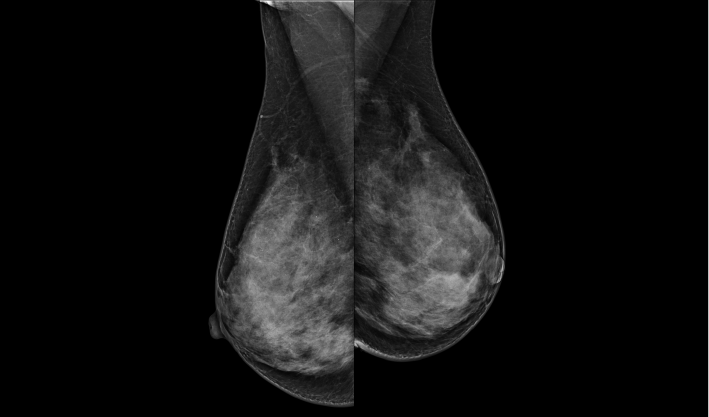

头尾位(CC位) 内外斜位(MLO位) 补充体位(根据需求)

致力于致密乳腺的早期癌变筛查和微钙化簇精准定性。